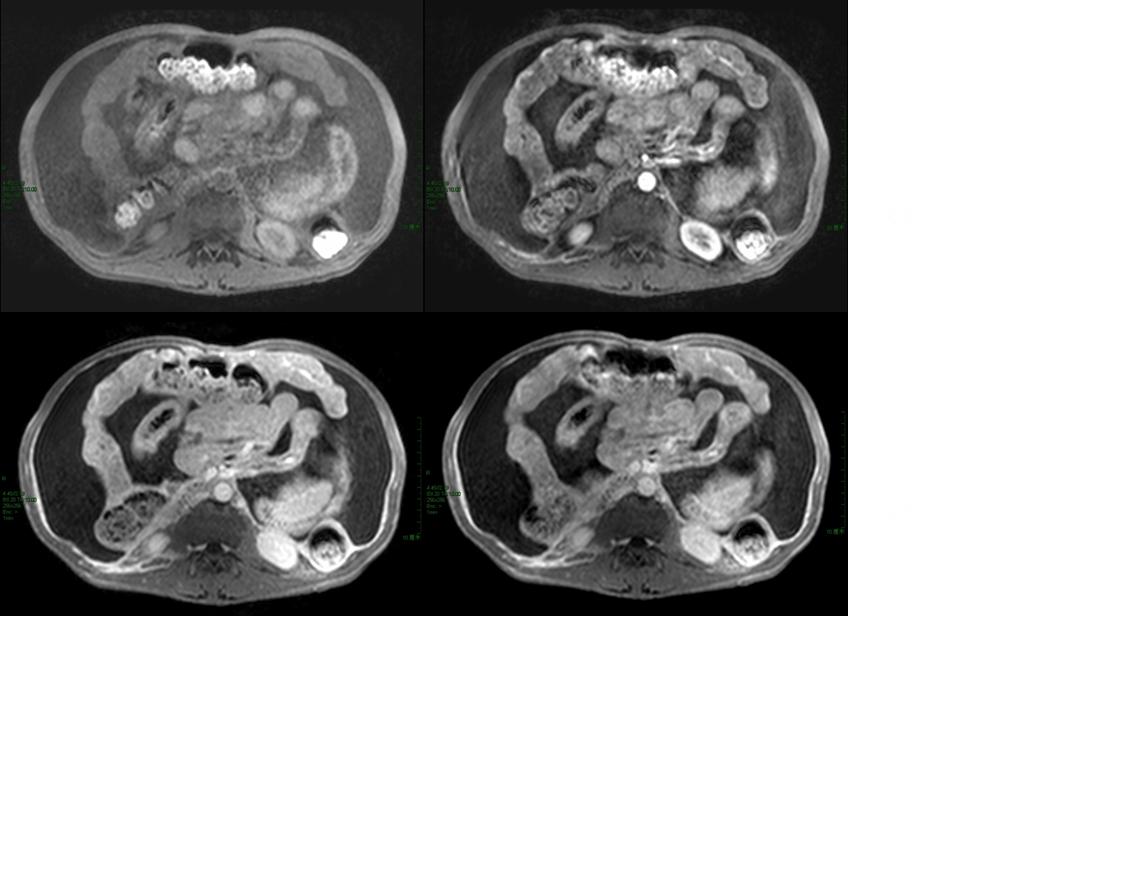

男性,47岁,乙肝病史十余年,无发热、腹痛,无恶性、呕吐,无下肢浮肿,否认结核病史,尘肺史 实验室检查:肝肾功能正常,afp、cea(—),腹水生化:黄色浊,李凡他实验(++++),间皮细胞85%,中性粒细胞5%,淋巴细胞10%;

右肾囊肿

大量腹水、脾门占位(长t1短t2为主混杂信号)------考虑为恶性肿瘤伴腹膜转移、腹水合并感染。

腹水很多,抽腹水检查发现间皮细胞增多

考虑为恶性肿瘤伴腹膜转移、腹水合并感染。